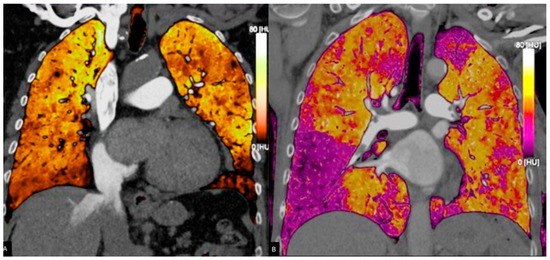

3.2. Dual Energy CT

3.2.1. Principles of DECT

3.2.2. Accuracy of DECT

- Cellina, M.; Cè, M.; Grimaldi, E.; Mastellone, G.; Fortunati, A.; Oliva, G.; Martinenghi, C.; Carrafiello, G. The role of dual-energy computed tomography (DECT) in emergency radiology: A visual guide to advanced diagnostics. Clin. Radiol. 2025, 83, 106836. [Google Scholar] [CrossRef]